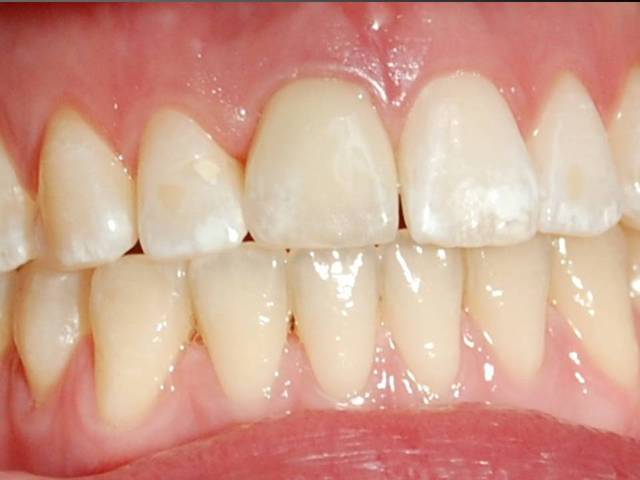

J'utilise la zircone depuis 7-8 ans,et je trouve que oui, la gencive est belle autour.

Par contre dans le dernier cas, je ne trouve pas que la gencive est belle, ell semble plutot inflammée...je crois que l'espace biologique n'est pas respecté.